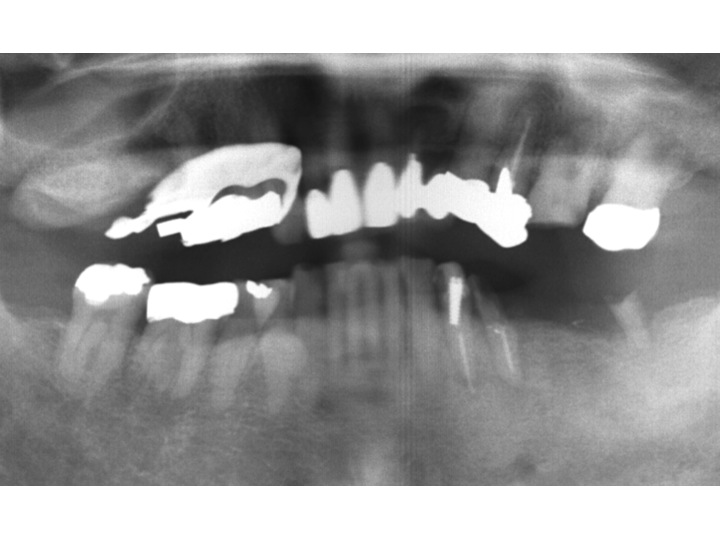

エムドゲイン(EMDOGAINTM®)は、歯周組織再生誘導材料と言われるものです。

スウェーデンのビオラ社で開発された歯周組織再生誘導材料です。

エムドゲインの主成分は子供の頃、歯が生えてくる時に重要な働きをするたんぱく質の一種です。

このエムドゲインをルートプレーニングを行い、汚染組織を除去した後、

歯の根に塗ることにより、歯の発生過程に似た環境を再現します。

その結果、骨や歯肉繊維を再生させるのです。